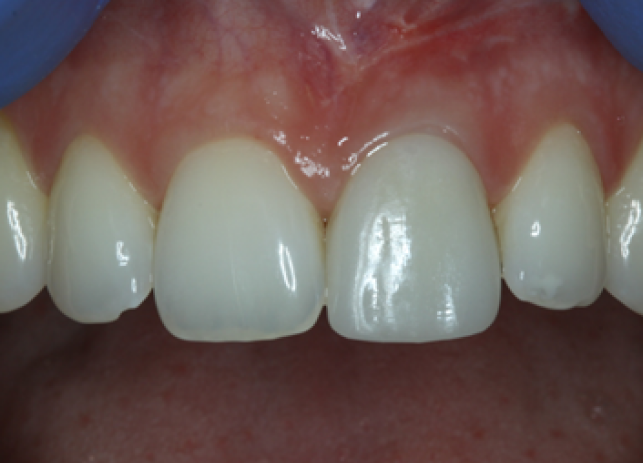

Рис. 9 и 10 после начального заживления временная коронка была адаптирована с помощью композита для тренировки и формирования мягких тканей, аналогично прилегающему правому центральному резцу. Нашей целью также было добиться одинаковой длины 11 и 21 зубов или выровнять высоту десны